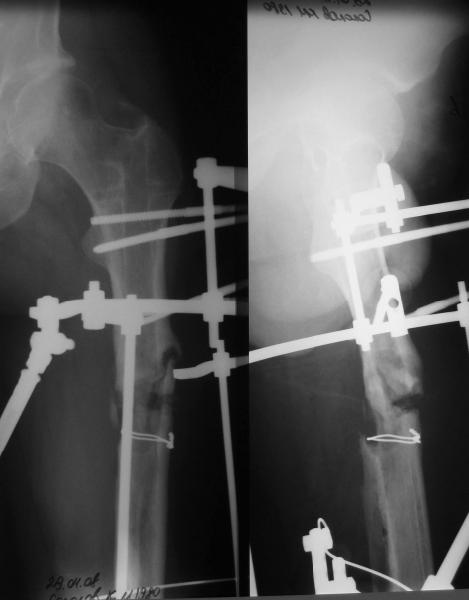

Пациент попал под наше наблюдение через 3 недели после первого остеосинтеза (фото 1). Учитывая, нестабильность остеосинтеза, выстоящий стержень закрыто перештифтовали (фото 2), через 3 месяца динамизация. К 5 месяцам имели укорочение 2 см, при том, что динамический винт стал статическим. От дальнейшей динамизации отказались, учитывая наличие контакта между фрагментами и возможность прогрессирования укорочения. К 1,5 года сращение не достигнуто (фото 3). Удалили гвоздь, выполнили дистракционный остеосинтез с целью стимуляции остеогенеза и компенсации укорочения (фото 4), потом закрыто перештифтовали после рассверливания (фото 5). На сегодняшний день, через 4 месяца после последней операции (фото 6) признаков регенерата нет, длина восстановлена, ходит без дополнительной опоры.

Возможные варианты: 1)подождать - однако регенерата не заметно 2)Снова потерять длину (динамизация, компрессирющий остеосинтез на этом гвозде, после перепроведения проксимальных винтов и копрессирующей заглушки, восстановление длины после сращения) 3)Костная пластика